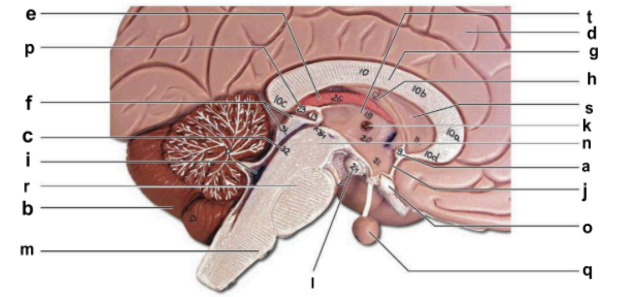

Identify the structure labeled “a” in the image.

anterior commissure

Identify the structure labeled “b” in the image.

cerebellum

Identify the structure labeled “c” in the image.

cerebral aqueduct

Identify the structure labeled “d” in the image.

cerebral hemisphere

Identify the structure labeled “e” in the image.

choroid plexus

Identify the structure labeled “f” in the image.

corpora quadrigemina

Identify the structure labeled “g” in the image.

corpos callosum

Identify the structure labeled “h” in the image.

fornix

Identify the structure labeled “i” in the image.

fourth ventricle

Identify the structure labeled “j” in the image.

hypothalamus

Identify the structure labeled “k” in the image.

interthalamic adhesion

Identify the structure labeled “l” in the image.

mammilary body

Identify the structure labeled “m” in the image.

medulla oblongata

Identify the structure labeled “n” in the image.

midbrain

Identify the structure labeled “o” in the image.

optic chiasma

Identify the structure labeled “p” in the image.

pineal gland

Identify the structure labeled “q” in the image.

pituitary gland

Identify the structure labeled “r” in the image.

pons

Identify the structure labeled “s” in the image.

septum pellucidum

Identify the structure labeled “t” in the image.

thalamus